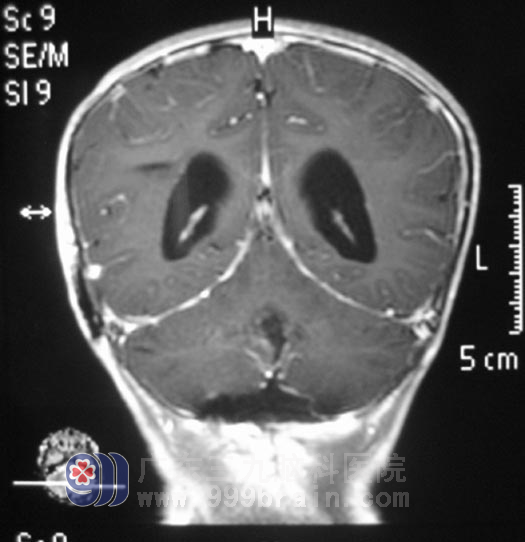

为了给儿子找到最好的医院治疗,小瀚的父亲四处打听,咨询亲朋好友、上网搜索、四处打电话咨询……最终,他选定了广东三九脑科医院。11月29日,小瀚在父母的陪同下来到广东三九脑科医院求医,并找到了神经外五科 鲁明 主任。入院后,鲁明 主任详细了解了小瀚的病情,结合其头颅检查,凭借多年的脑肿瘤诊疗经验,初步诊断为:四脑室占位性病变,梗阻性脑积水。鲁明 主任指出:凭其影像学表现上看,长在小瀚脑子里的肿瘤可能恶性程度较高。12月1日,小瀚在全麻下接受了“右侧脑室腹腔分流术+四脑室内占位切除术”。术程顺利,术后,小瀚头痛呕吐症状消失了,四肢肌力也逐步恢复到正常。术后病理报告示:髓母细胞瘤WHO IV级。术后,小瀚在广东三九脑科医院肿瘤综合治疗中心接受了放化疗,目前已经康复回家。http://www.999brain.com

术后肿瘤消失